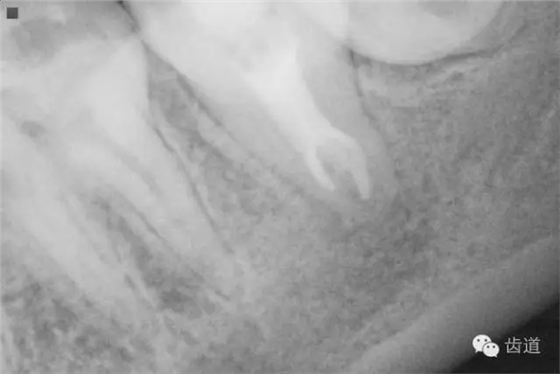

2. 術(shù)前X片

可見(jiàn)37根管影像清晰,根中上三分之二粗大,根尖三分一分為近遠(yuǎn)中兩根管,形態(tài)均呈弧形,根尖周膜連續(xù)性中斷,根尖周透射影明顯